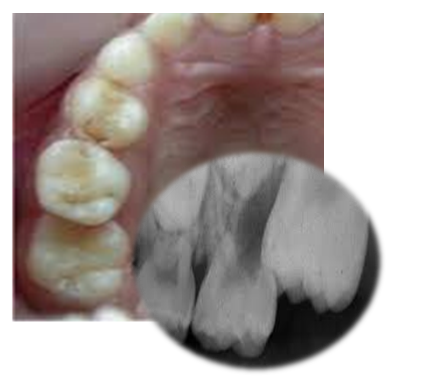

Poseban oblik nepravilnosti nicanja odnosi se na nepravilno kretanje prvog stalnog molara(“šestica”) previše napred, pri čemu vrši pritisak na mlečni molar(“petica”). (Slika 4). To može dovesti do topljenja mlečnog zuba, njegovog ranijeg gubitka, što opet uslovljava dalje pomeranje “šestice” i zatvaranje prostora u koji treba da iznikne drugi premolar(“stalna četvorka”). To zahteva složeno ortodontsko lečenje, a ponekad i vađenje zdravog stalnog zuba.

Slika 4. Topljenje(resorbcija) mlečnog zuba prilikom nicanja stalne “šestice”

Ova nepravilnost se često ne primećuje, jer nije jasno vidljiva za laika, a samo ponekad može da bude praćena tupim bolom. Zbog toga su veoma značajni redovni pregledi u periodu nicanja prvih stalnih zuba.